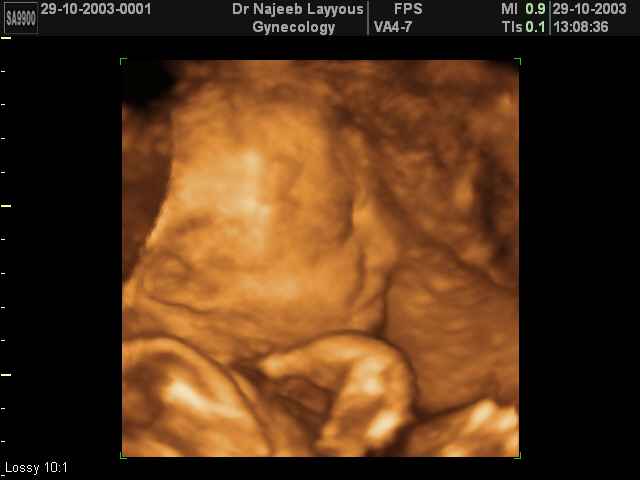

- 3D Fetal Profile Ultrasound Scan Photos